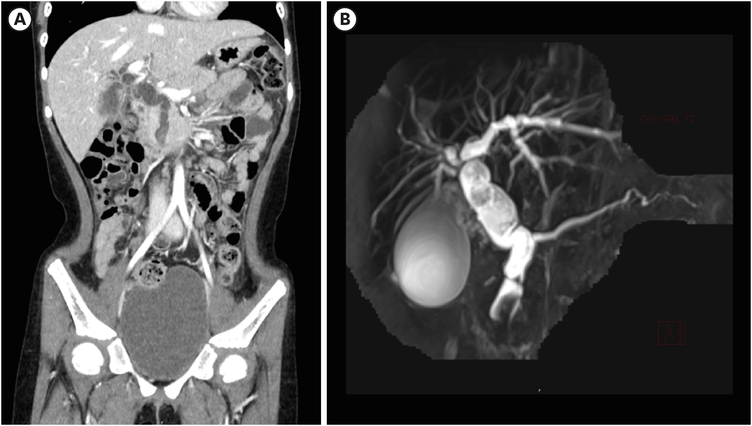

A 7-year-old girl visited the pediatric department of Asan Medical Center for endoscopic retrograde cholangiopancreatography (ERCP) to remove a distal common bile duct (CBD) stone. She was previously healthy and visited a nearby hospital due to abdominal pain and vomiting lasting for 13 days, and jaundice progressed the day before hospital visit. Computed tomography (CT) revealed tortuous dilatation of the extrahepatic bile duct abruptly narrowed in the distal CBD level with several distal CBD stones and anomalous pancreaticobiliary ductal union (APBDU, P-C type). The common channel was measured as 1.9 cm in length. These findings suggested type I CC related to APBDU. Secondary cholecystitis, cholangitis, and pancreatitis were additionally found (Fig. 1A). The same findings were confirmed on magnetic resonance imaging (Fig. 1B). After failure of the first ERCP at the previous hospital, she kept non per oral for one week, but symptoms and lab findings were never relieved (Table 1). So, she was determined to transfer to Asan Medical Center. ERCP was performed. Both pancreatic and CBD were successfully cannulated, and a 10 Fr. Endoscopic retrograde biliary drainage stent was retained in the bile duct for remnant stone excretion. No residual stone was found in follow-up CT in 3 days post ERCP (Fig. 2). Serum levels of liver enzymes, bilirubin, and amylase/lipase decreased to the normal range. Two months later, robotic CC excision and Roux-en-Y hepaticojejunostomy were performed. Severe adhesion and fibrosis around the CC reflecting chronic inflammation were noted. Type I CC was identified, and CBD was resected proximally above the cystic duct and distally at the upper border of the pancreas head. The patient recovered without acute complications. In ultrasonography of post-operative day (POD) 7, no abnormal finding was observed except a small fluid collection around hepaticojejunostomy. She was discharged on POD 9. In the permanent biopsy, edematous mucosal change of gallbladder (GB) and cystic duct was observed, but the diameter of the cystic duct was within the normal range (0.4 cm). In microscopic findings, papillary hyperplasia was identified. The resected CC was 2 cm in length and 2 cm in the widest circumference. It was pathologically confirmed as a CC, accompanying fibrosis and wall thickening changes of CBD, and low-grade BilIN was identified from the resected CC (Figs. 3 and 4). Papillary hyperplasia in GB suggests chronic inflammation in the biliary system due to CC such as BilIN. There was no involvement in the cystic duct and GB as in Type VI.

Fig. 1

CT and MRCP at initial diagnosis. (A) Contrast-enhance CT was performed, and it revealed severe dilatation of extrahepatic bile duct with wall thickening and narrowing in the distal CBD level. Also, mild dilatation of both proximal intrahepatic bile ducts were observed. Several distal CBD stones were found. (B) In MRCP, anomalous pancreaticobiliary ductal union (1.9 cm in length, C-P type) was observed.

CT, computed tomography; MRCP, magnetic resonance cholangiopancreatography; CBD, common bile duct.